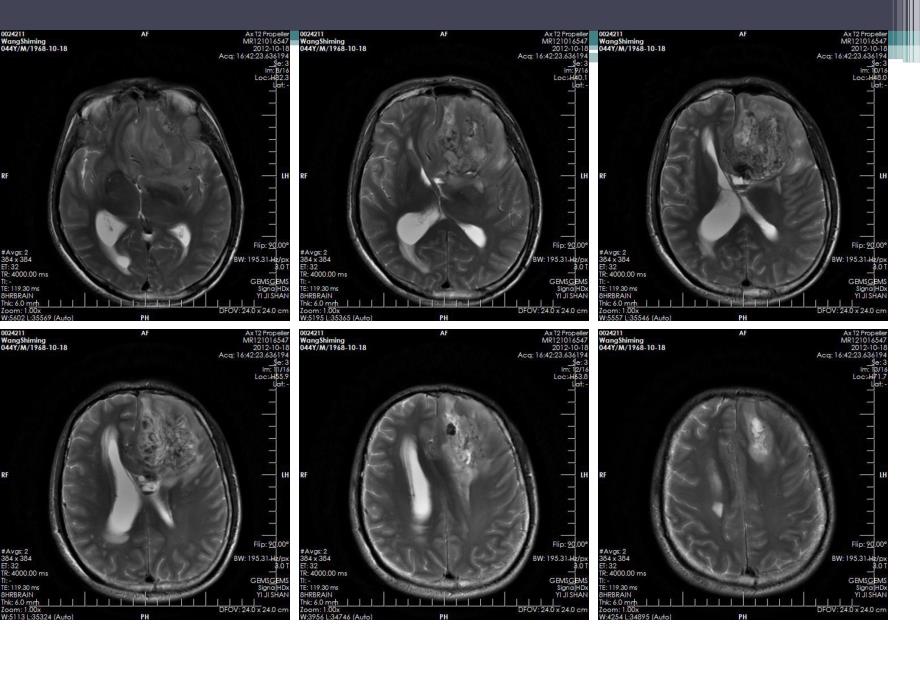

1、病例1男,44岁。主诉:头晕十余天,加重一天。查体:神清,嗜睡,四肢肌力IV级,余无 特殊。病理诊断:病理诊断:(左侧额叶)间变型少突胶质星形细胞瘤(相当于WHO 级)。免疫组化标记结果,瘤细胞:LCA(-)、AE1/AE3(-)、p53(-)、EMA(-)、S-100(+)、CD34(-)、GFAP(+)、PR(-)、Ki-67:5%(+)。概念:概念:2007年WHO颁布的分类方法巾,少突胶质细胞起源的肿瘤(oligodendroglial tumours)属于神经上皮性肿瘤,分为少突胶质细胞瘤(oligodendroglioma,grade II)和间变性少突胶质细胞瘤(anaplast

2、icoligodendroglioma,grade)。少突胶质细胞起源的肿瘤占成人脑胶质瘤的33%,是继多形性胶质母细胞瘤之后,第二位的成人脑胶质瘤。相对于同级别的星形细胞瘤而言,少突胶质细胞瘤的临床过程较长,预后较好。85%位于幕上,好发于额叶,表浅部位 发病高峰3545岁,病程较长 男性稍多于女性 临床表现:病人以长时间局灶性癫痫为首发症状,其他症状和体征以肿瘤的发生部位而定。病理特征:病理特征:镜下肿瘤细胞呈蜂窝状,细胞大小、形态相似,排列均匀一致,细胞核呈规则球形,核周透明空泡环绕形成“煎蛋样”形态,间质少,间质内散布丰富的树杈样或鹿角样血管,常有钙化,常发生于肿瘤血管壁上,亦可发生于

3、肿瘤内或瘤外组织。影像学表现:CT:平扫平扫多数呈低密度,少数略高 钙化多见,典型者表现为弯曲条状钙化灶占肿瘤大部 囊变、出血少见 占位效应轻,无水肿或轻度水肿增强增强大多数无强化,少数轻度强化MRIMRI平扫平扫长或等T1长T2 钙化在T1/T2上均呈低信号 肿瘤多为圆形或椭圆形,边界清楚,瘤周水肿无或轻度,占位效应轻。增强增强无或轻度强化鉴别诊断鉴别诊断 血管母细胞瘤:平扫很难鉴别,增强明显。MR可见血管留空效应?钙化?毛细胞型星形细胞瘤:常发生于颞叶,囊变多见。节细胞瘤:常发生于颞叶,囊变、钙化常见。脑膜瘤 室管膜瘤病例2男,70岁。主诉:记忆力减退待查。查体:神清,精神可。病理结果:病